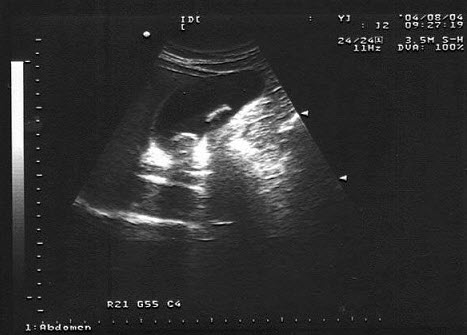

10、单项选择题

女,40岁,有时右上腹隐痛2年余。结合超声声像图,最可能的诊断为()

A.肝血管瘤

B.肝脓肿

C.小肝癌

D.转移性肝癌

E.肝囊肿